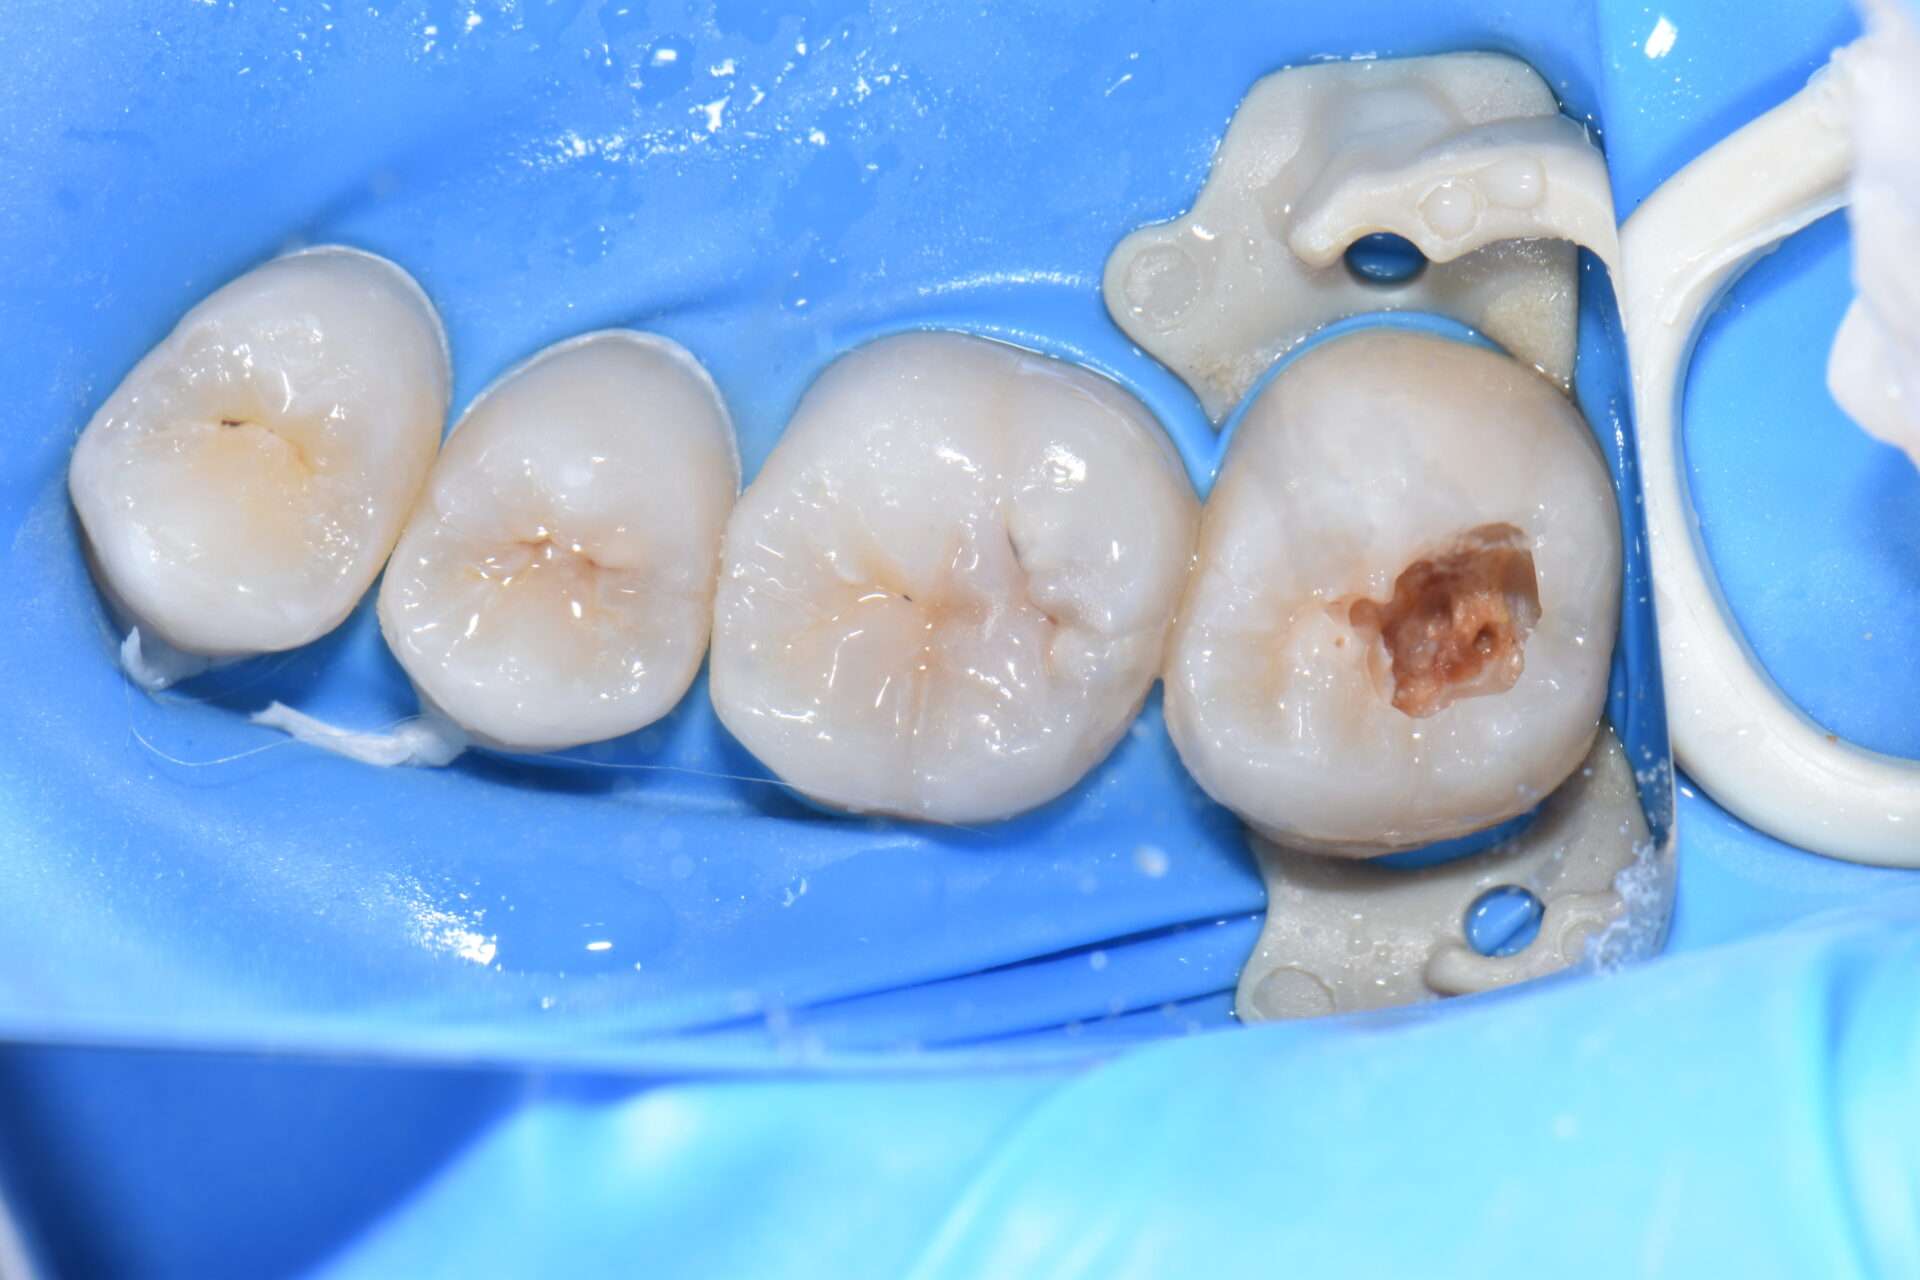

術前 歯科健診と歯のクリーニングで来院。第二大臼歯に虫歯が見つかりました。

無自覚無症状で大変小さな虫歯に見えますが実は大きな虫歯です。